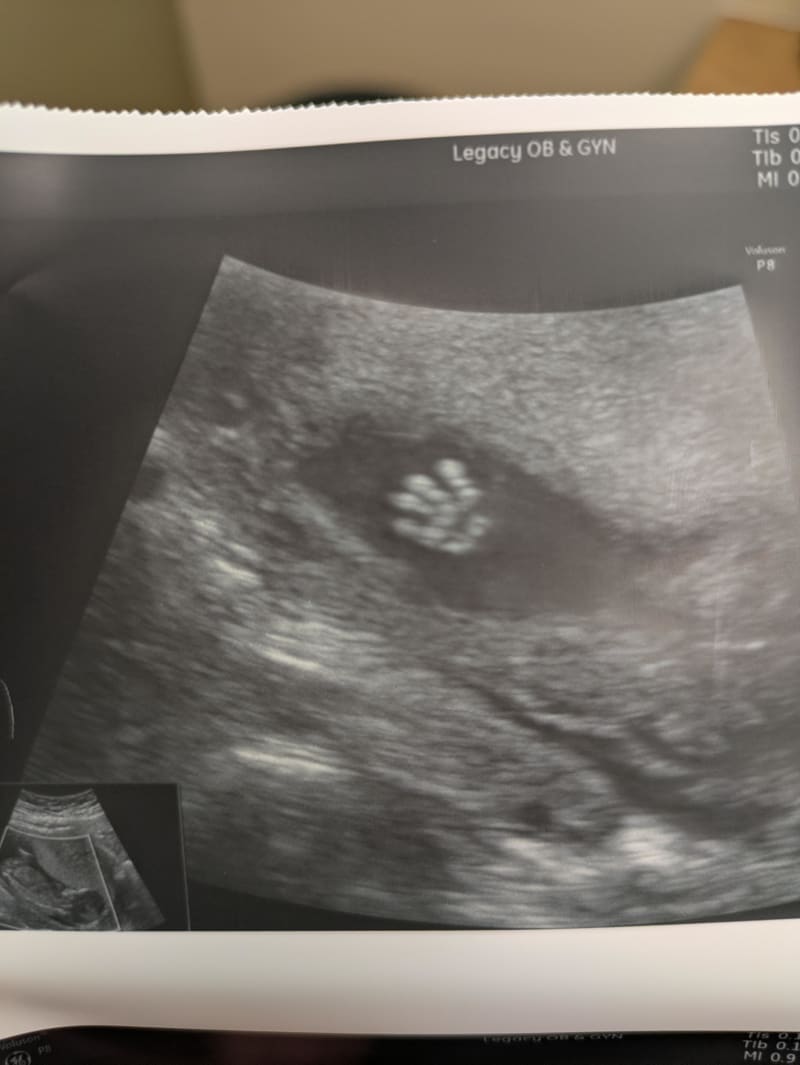

After years of trying to conceive and investing thousands of dollars in fertility treatments and IVF procedures, the expectant parents finally received the gift they'd been hoping for. The mother, sharing her joy on social media, posted an ultrasound image that captured an extraordinary moment: their little one appeared to be waving at them from inside the womb.

"They're waving hello," she wrote, overwhelmed with emotion. In the comments, she added, "I am absolutely hysterical right now," capturing the raw joy that many who have struggled with infertility understand deeply. While acknowledging it might not be the "best" technical photo of their baby, she declared it her absolute favoriteāa testament to how the most meaningful moments often transcend technical perfection.